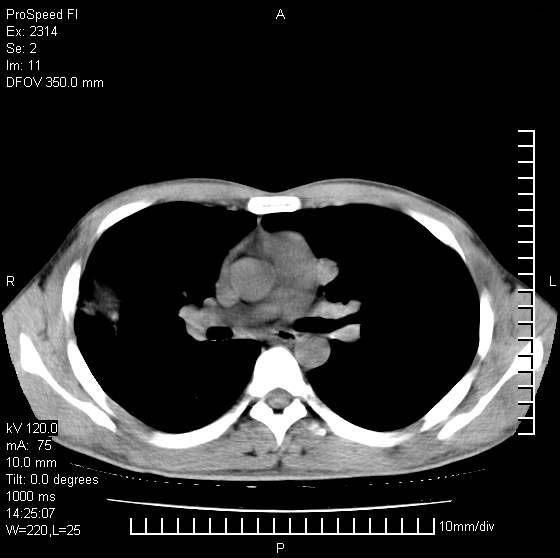

男性,再生障碍性贫血,入院前发热10天,最高40c,右侧胸痛,外院ct示右上,中肺边缘模糊的球性影(就是我现在图中标示的范围),考虑炎症,在我院使用头孢呋辛,洛美沙星10天,高烧消退,自感下午稍有发热,但今天ct示右上,中肺病灶明显扩大,还是考虑炎症,看其中的球型影是否霉菌感染??,是否能排除结核?

右肺中叶外侧段病变,上缘界限不清,下缘锐利,以段性发病为主,内见巨大空洞及空洞内容物,结合病史首先考虑:化脓性肺炎。不除外霉菌感染!

片状高密度影内见空洞影,内可见球形软组织密度影,并有新月征,考虑霉菌感染.

支持右肺上叶、中叶外侧段节段性肺炎伴脓肿形成。